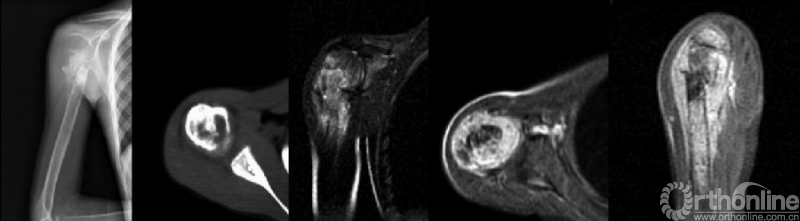

骨肉瘤是儿童和青少年最常见的原发恶性骨肿瘤,其预后差。目前骨肉瘤患者5年生存率约为60-70%,转移患者则更低。多种因素已被证实影响骨肉瘤患者预后。病理性骨折(pathologic fractures,PFs)是骨肉瘤患者常见并发症之一(图1),但PFs对骨肉瘤患者预后的影响以及针对该类患者治疗方式的选择一直以来存在争议。因此,有必要针对这一问题进行文献回顾和讨论。

图1. 右肱骨近端骨肉瘤的病理性骨折(来自Xie L,J Surg Oncol.2012.)